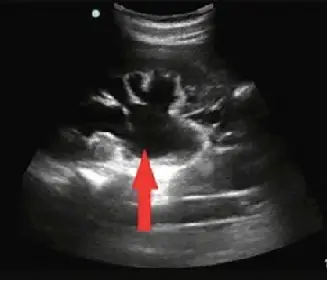

腎臟超音波影像如附圖,最有可能的診斷為何?

- 切面與結構:這是一張腎臟的超音波長軸(longitudinal)切面影像。

- 回音特徵:在腎臟中央的腎竇(renal sinus)區域,原本應充滿高回音(hyperechoic,偏白)的脂肪與結締組織,此圖中卻被大範圍的無回音(anechoic,黑色)區域取代,代表有明顯的液體積聚。

- 解剖對應與特殊徵象:紅色箭頭明確指向擴張的腎盂(renal pelvis)。這些無回音的液體區域向外延伸並相連,顯示出多個擴張的腎盞(dilated calyces)。這種相互連通、分支狀的擴張集尿系統,在超音波上呈現典型的「熊掌徵」(bear's paw sign)或花椰菜狀外觀,為中度至重度尿液積聚的表現。